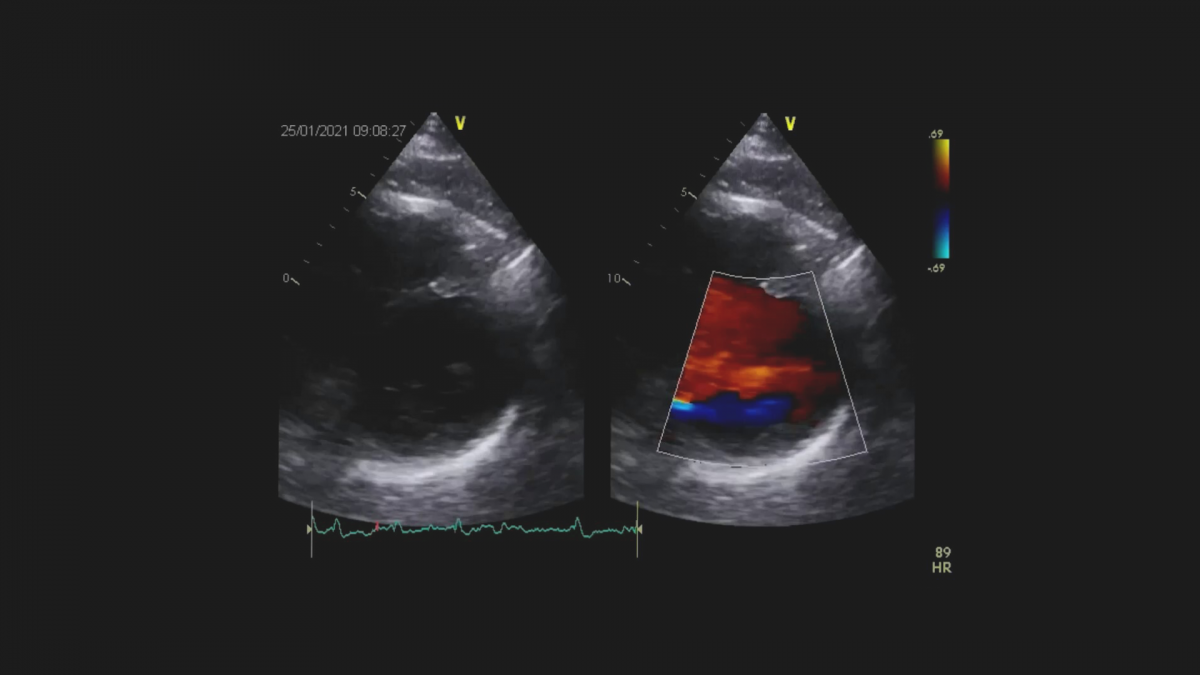

Dwoje pacjentów z objawami niewydolności serca, po przebytym zawale serca.

Dysfunkcja mięśnia lewej komory z czynnościową niedomykalnością mitralną.

Echokardiografia przezklatkowa.

Ocena regionalnej i globalnej funkcji skurczowej mięśnia lewej komory

Ocena niedomykalności mitralnej.